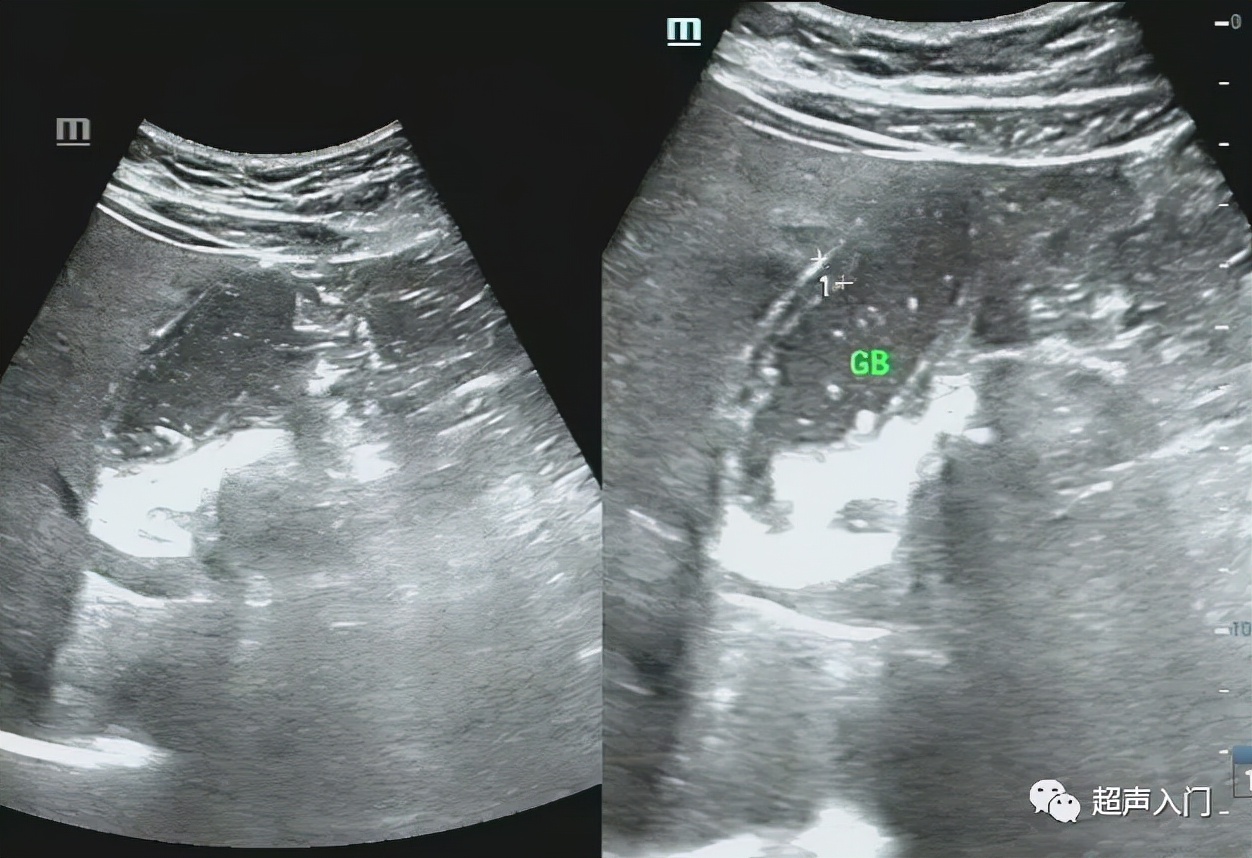

2、化脓性胆囊炎,也称蜂窝织炎性胆囊炎,胆囊肿大,囊壁充血水肿,明显增厚,胆汁混浊或呈脓性。胆囊与周围组织粘连,或形成胆囊周围脓肿。

脓性胆汁

3、坏疽性胆囊炎,胆囊极度肿大,如胆囊壁血液循环发生障碍时该处可发生出血坏死,甚至穿孔而并发局限性或弥漫性腹膜炎。若有产气杆菌感染,胆囊内可积气,但较少见,好发于老年及糖尿病患者。

但常规超声往往很难对其进行准确分类,囊内透声好并不代表没有化脓,如上图,囊内透声很好,但患者持续发热,胆囊置管后,抽出脓性胆汁。

3、胆囊切面无回声区内出现稀疏或密集的分布不均的细小或粗大回声斑点,呈云雾状,为胆囊积脓的表现。